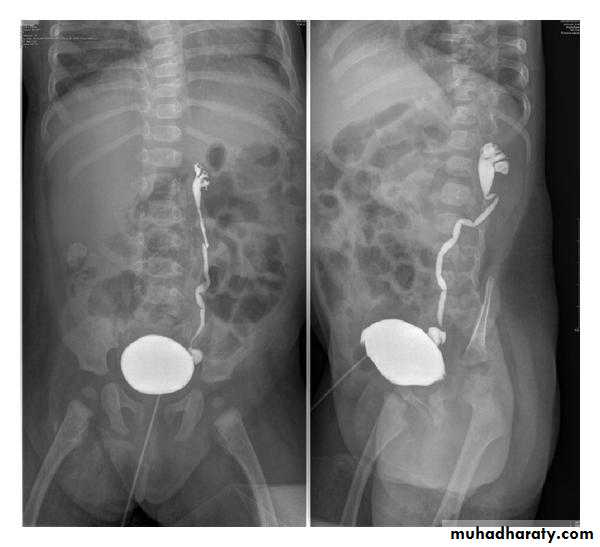

Voiding cystogram

• The UB is filled with iodinated contrast medium through a catheter… Films are taken during voiding via a fluoroscopy

• Indications are :

• Identify VUR

• Posterior uretheral valve

• Demonstrate the posterior urethera.